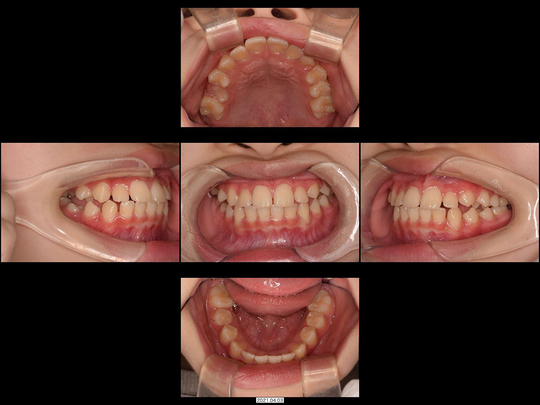

矯正後

歯列矯正用咬合誘導装置(ムーシールド)  終了

画像をクリックで拡大

固定式拡大装置 開始